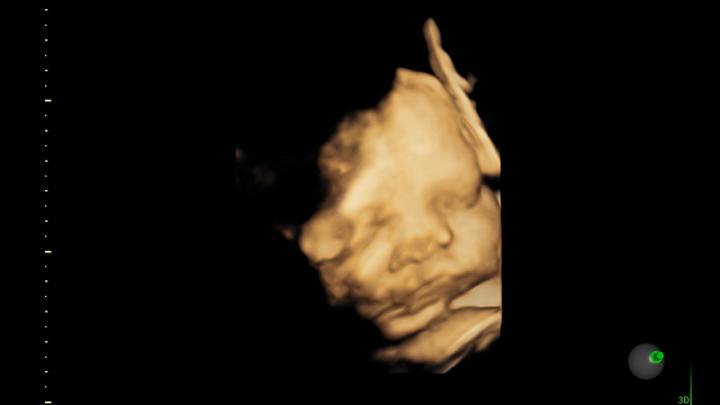

After two years of it just being us, one morning I found out that I was pregnant. To be honest I was terrified, having PCOS I had come to terms with believing that I might not have children in this lifetime. But God blessed me with the one thing I thought I couldn’t have. I told my husband and, just as I did, he couldn’t believe it. We cried and we panicked, but in the end we were so happy to start building our family together.

It’s been week after week and now I find myself 38 weeks along expecting our beautiful baby boy any day now. Im thankful to work somewhere that provides paid maternity leave but ultimately it’s not enough to get us by. And as of very recently my husband has unfortunately lost his job suddenly so now it feels as if we are stuck in a deep hole.